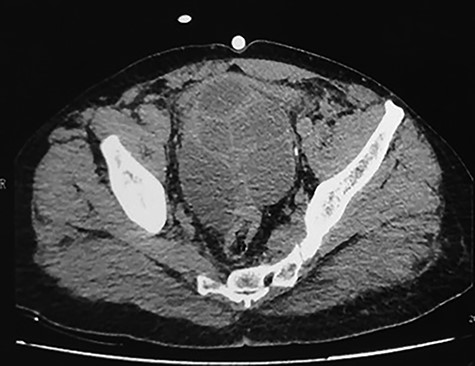

The patient was seen on Day 15, 1 month, 3 months, 9 months postoperatively. The control CT scans made at 3 and 9 months postoperatively had shown no abnormalities without any residual mass (Fig. 6).

Control CT scan at 9 months postoperatively: the bladder and prostate are normal in appearance and there is no residual mass.